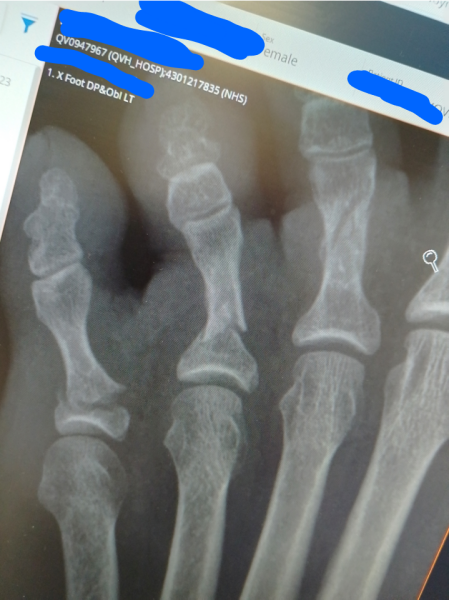

GingerLiberalFeminist · 22/12/2023 13:33

I broke three, the little one and two in plus two tarsal bones in April. Id fallen down the stairs and my whole weight went on them on the door frame. I felt sick and couldn't put any weight on them. Went to hospital and they confirmed the breaks, strapped them up and gave me a moon boot. I couldn't stand for long periods for about six weeks and when I put my winter boots on this year they pinched as my toes are wonky 😂

Oh god that must have been so unbelievably painful! That x-ray makes me feel nauseous thinking about how much that must have hurt!

GingerLiberalFeminist · 23/12/2023 07:46

@MoonlightMemories

Thanks, it was definitely one of the worst pains I've felt! It's the nausea I remember the most though.